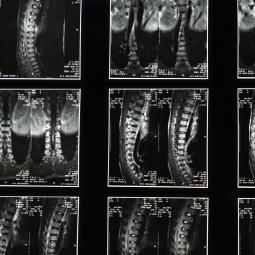

Vi kan bruge billeddiagnostik som CT til at finde ud af hvad mennesker fejler - men kan det også opklare et mord? CT skannere bliver i tiltagende grad brugt i retsmedicinen til at supplere, og i nogle tilfælde erstatte den klassiske obduktion. Men! Det at skanne et levende menneske er ikke det samme som at skanne en afdød. Især hvis det er gået noget tid, siden døden er indtruffet. Retsmedicinsk Institut på SDU og Radiografuddannelsen på UCL indgik derfor et samarbejde om hvordan vi kunne forbedre CT skanninger af afdøde, og derved, forbedre muligheden for at finde dødsårsagen - og om den var naturlig. Det kom der nogle helt særlige problemstillinger ud af.